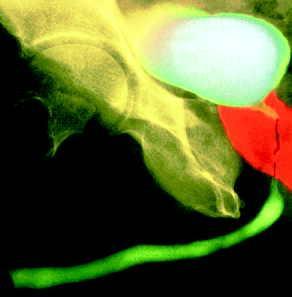

LA RÉTENTION AIGUË D'URINES, définie par l'incapacité d'uriner de façon volontaire, est une des principales complications de l'hypertrophie bénigne de la prostate (HBP). Elle entraîne une distension vésicale douloureuse nécessitant une prise en charge thérapeutique urgente. Celle-ci implique une hospitalisation pour décompression vésicale par sondage vésical (le plus souvent transurétral, plus rarement par ponction sus-pubienne) et éventuellement un geste chirurgical.

La première phase avait pour objectif d'évaluer l'efficacité de l'alfuzosine (Xatral LP 10 mg) versus placebo sur le retour à des mictions spontanées après sondage de patients ayant un globe vésical compris entre 500 et 1 500 ml, la deuxième phase était destinée à évaluer l'efficacité de Xatral LP 10 mg en prévention secondaire sur les récidives de rétention aiguë d'urine.

Lors de la première phase, les patients ont été répartis par randomisation en deux groupes : dans l'un, les patients recevaient l'alfuzosine à la posologie de 10 mg par jour en une seule prise pendant deux à trois jours dès la pose de la sonde urinaire et jusqu'à son retrait ; dans l'autre, un placebo. Les résultats mettent en évidence les bénéfices apportés par l'alfuzosine 10 mg : le pourcentage de patients ayant des mictions spontanées après retrait de la sonde atteint 61,9 % dans le groupe alfuzosine contre 47,9 % dans le groupe placebo (p = 0,012).